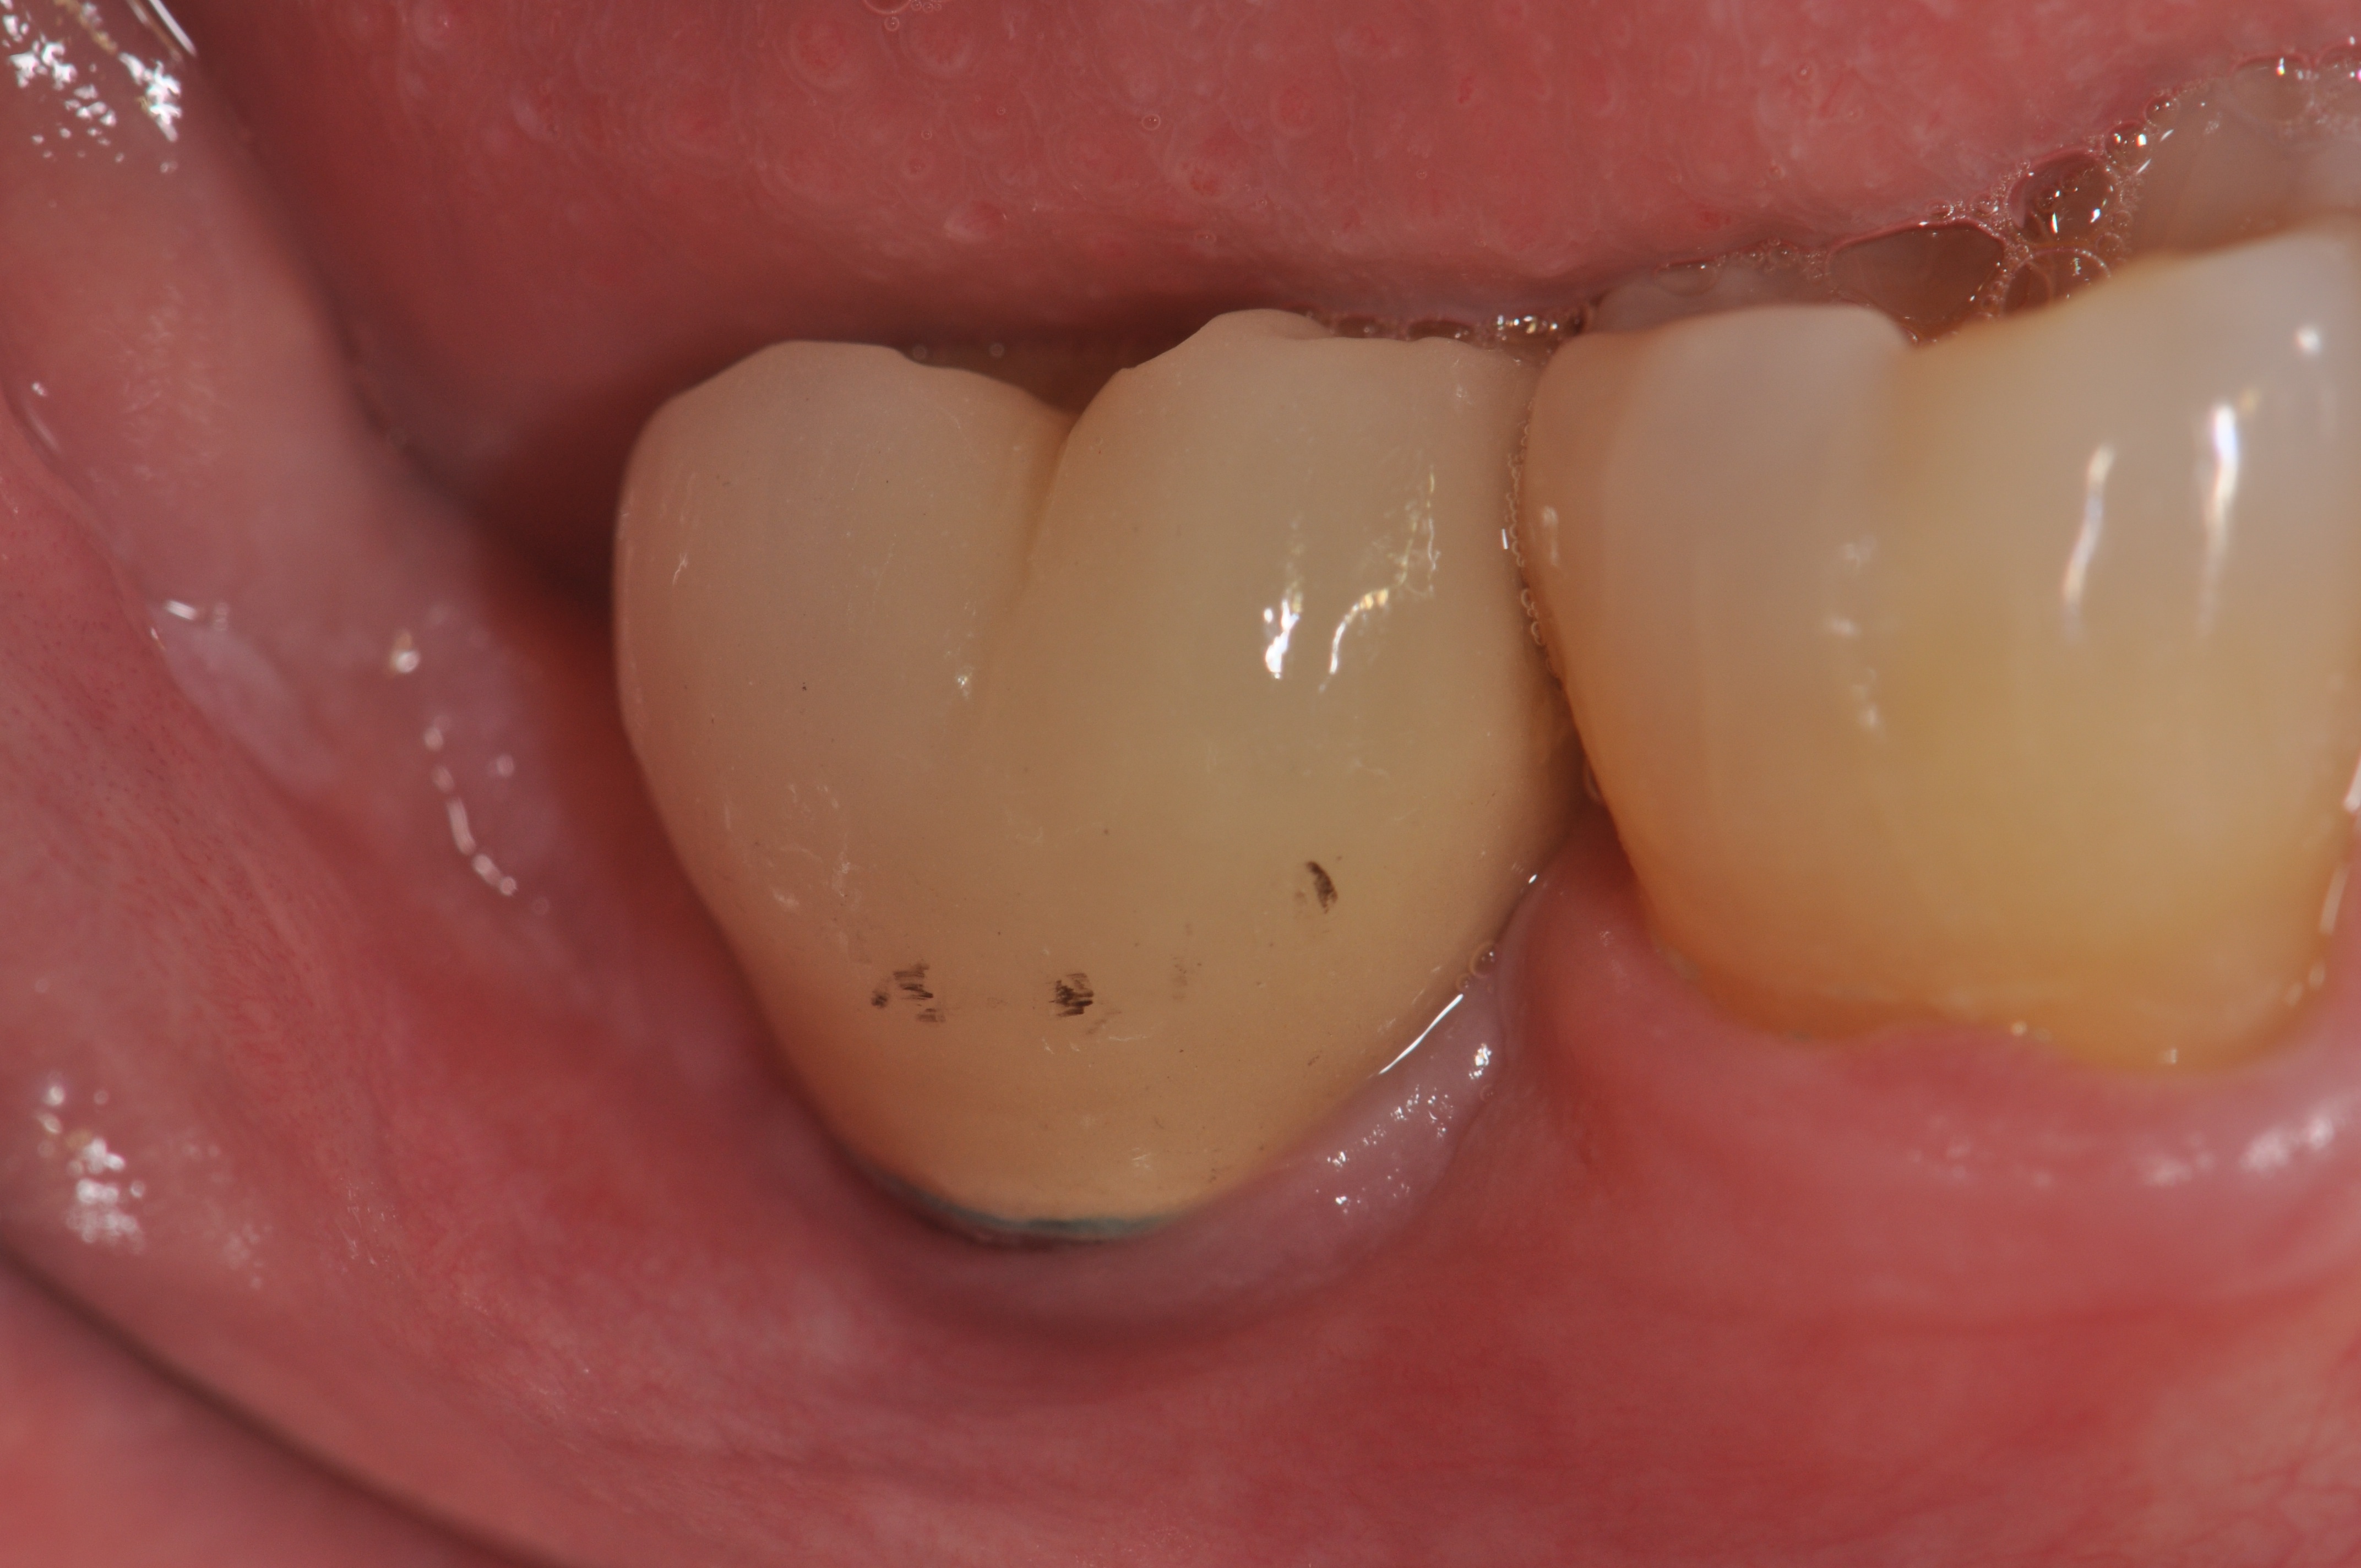

At 1 year following treatment, probing depths are now 3 mm with an absence of bleeding.

Figure 6

Figure 7